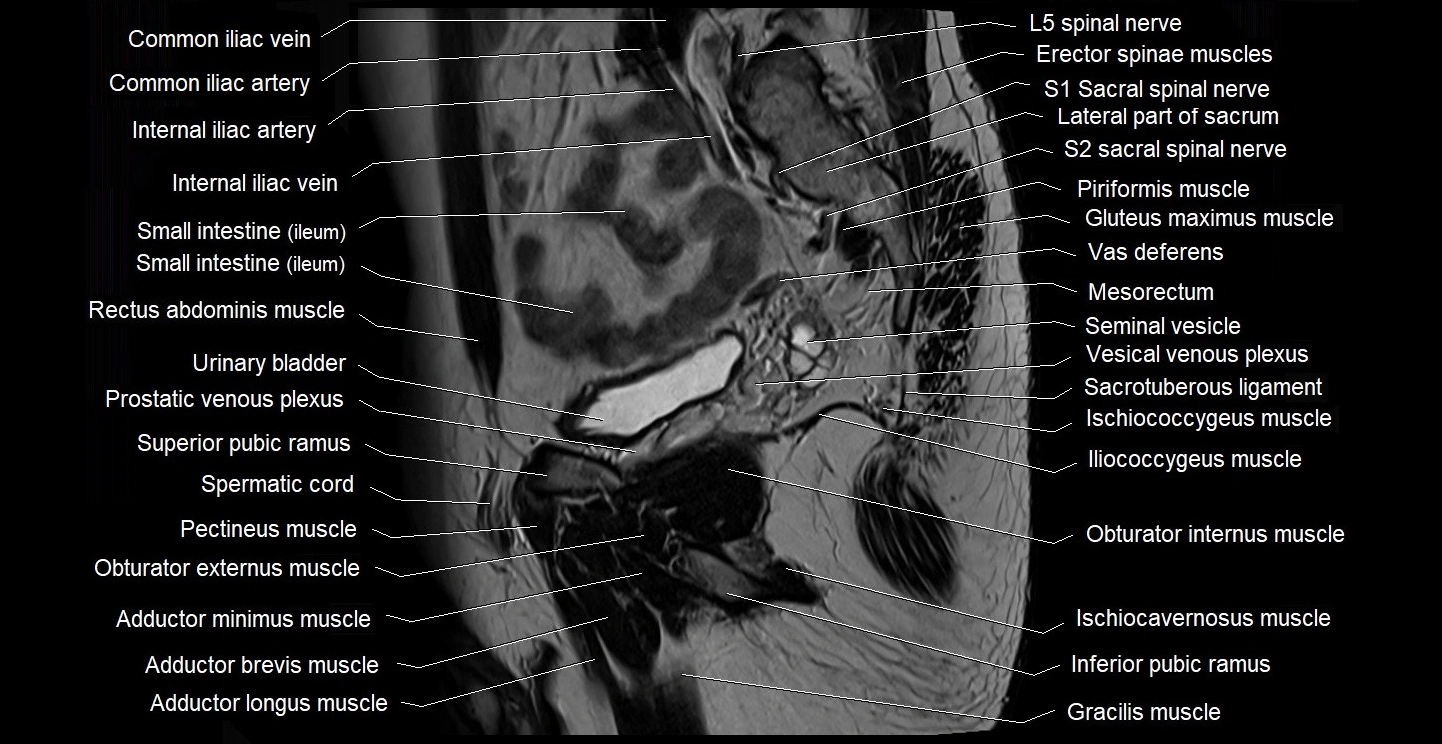

- Common iliac vein

- Erector spinae muscles

- Gluteus maximus muscle

- Gracilis muscle

- Iliococcygeus muscle

- Iliopsoas muscle

- Inferior pubic ramus

- Internal iliac artery

- Internal iliac vein

- Ischiocavernosus muscle (Male)

- Ischiococcygeus muscle

- Levator ani muscle

- Mesorectum

- Obturator internus muscle

- Pectineus muscle

- Piriformis muscle

- Prostatic urethra

- Puborectalis muscle

- Rectum

- Sacral plexus

- Sacrotuberous ligament

- Sartorius muscle

- Seminal vesicle

- Spermatic cord

- Superior pubic ramus

- Transitional zone of prostate

- Vas deferens

- Vesical venous plexus